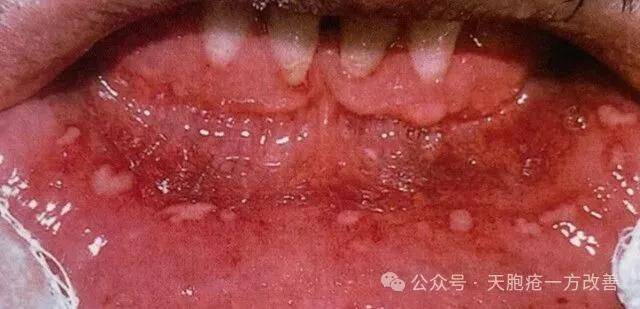

江苏患者李女士,3 年前确诊寻常型天疱疮,口腔黏膜、胸背部陆续出现水疱,水疱破溃后形成糜烂面,伴随明显疼痛,无法正常进食。她起初采用激素治疗,水疱数量暂时减少,但停药后迅速复发,还出现了满月脸、下肢水肿、血糖升高等副作用。

2022 年秋季,李女士开始服用健脾祛湿方剂。用药 1 个月后,口腔糜烂面逐渐愈合,能正常进食流质食物,胸背部新出水疱数量减少;用药 3 个月后,皮肤水疱基本消退,糜烂面完全愈合,疼痛、瘙痒症状消失,各项指标恢复正常,停药随访 1 年未复发。